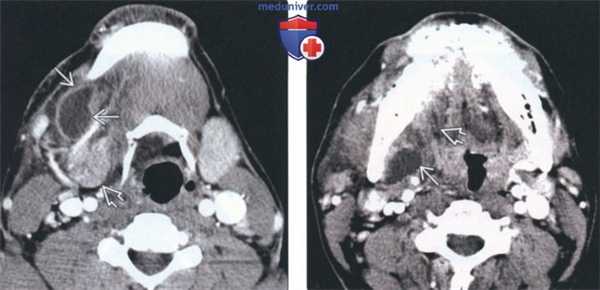

(Слева) КТ с КУ, аксиальная проекция. Крупная простая ранула В, деформирующая правое подъязычное пространство и смещающая челюстно-подъязычную мышцу в латеральную сторону. Утолщения стенок или накопления в них контраста нет, что говорит об отсутствии воспаления.

(Справа) КТ с КУ, коронарная проекция. Челюстно-подъязычная мышца В смещена книзу и латерально крупной, тонкостенной однокамерной кистой В. Простая ранула выглядит идентично эпидермоидной кисте подъязычного пространства. Для постановки диагноза требуется биопсия или четкий анамнез (при врожденной кисте).

2. КТ при рануле:

• КТ с КУ:

о ПрР:

- Однокамерное кистозное образование низкой плотности, незначительно накапливающее контраст в своих стенках

- Может проникать в подъязычное пространство другой стороны (форма подковы)

о ПР:

- Признак хвоста: спавшаяся подъязычная часть

- Располагается кзади от челюстно-подъязычной мышцы: хвост медиальнее челюстно-подъязычной мышцы, тело чаще медиальнее поднижнечелюстной железы

- Может распространяться в латеральную сторону через дефект в челюстно-подъязычной мышце (более частый вариант): хвост в передней части подъязычного пространства, тело обычно кпереди от поднижнечелюстной железы

о Инфицированная ранула (в настоящий момент или в прошлом):

- Растянутая киста с плотными стенками, накапливающими контраст